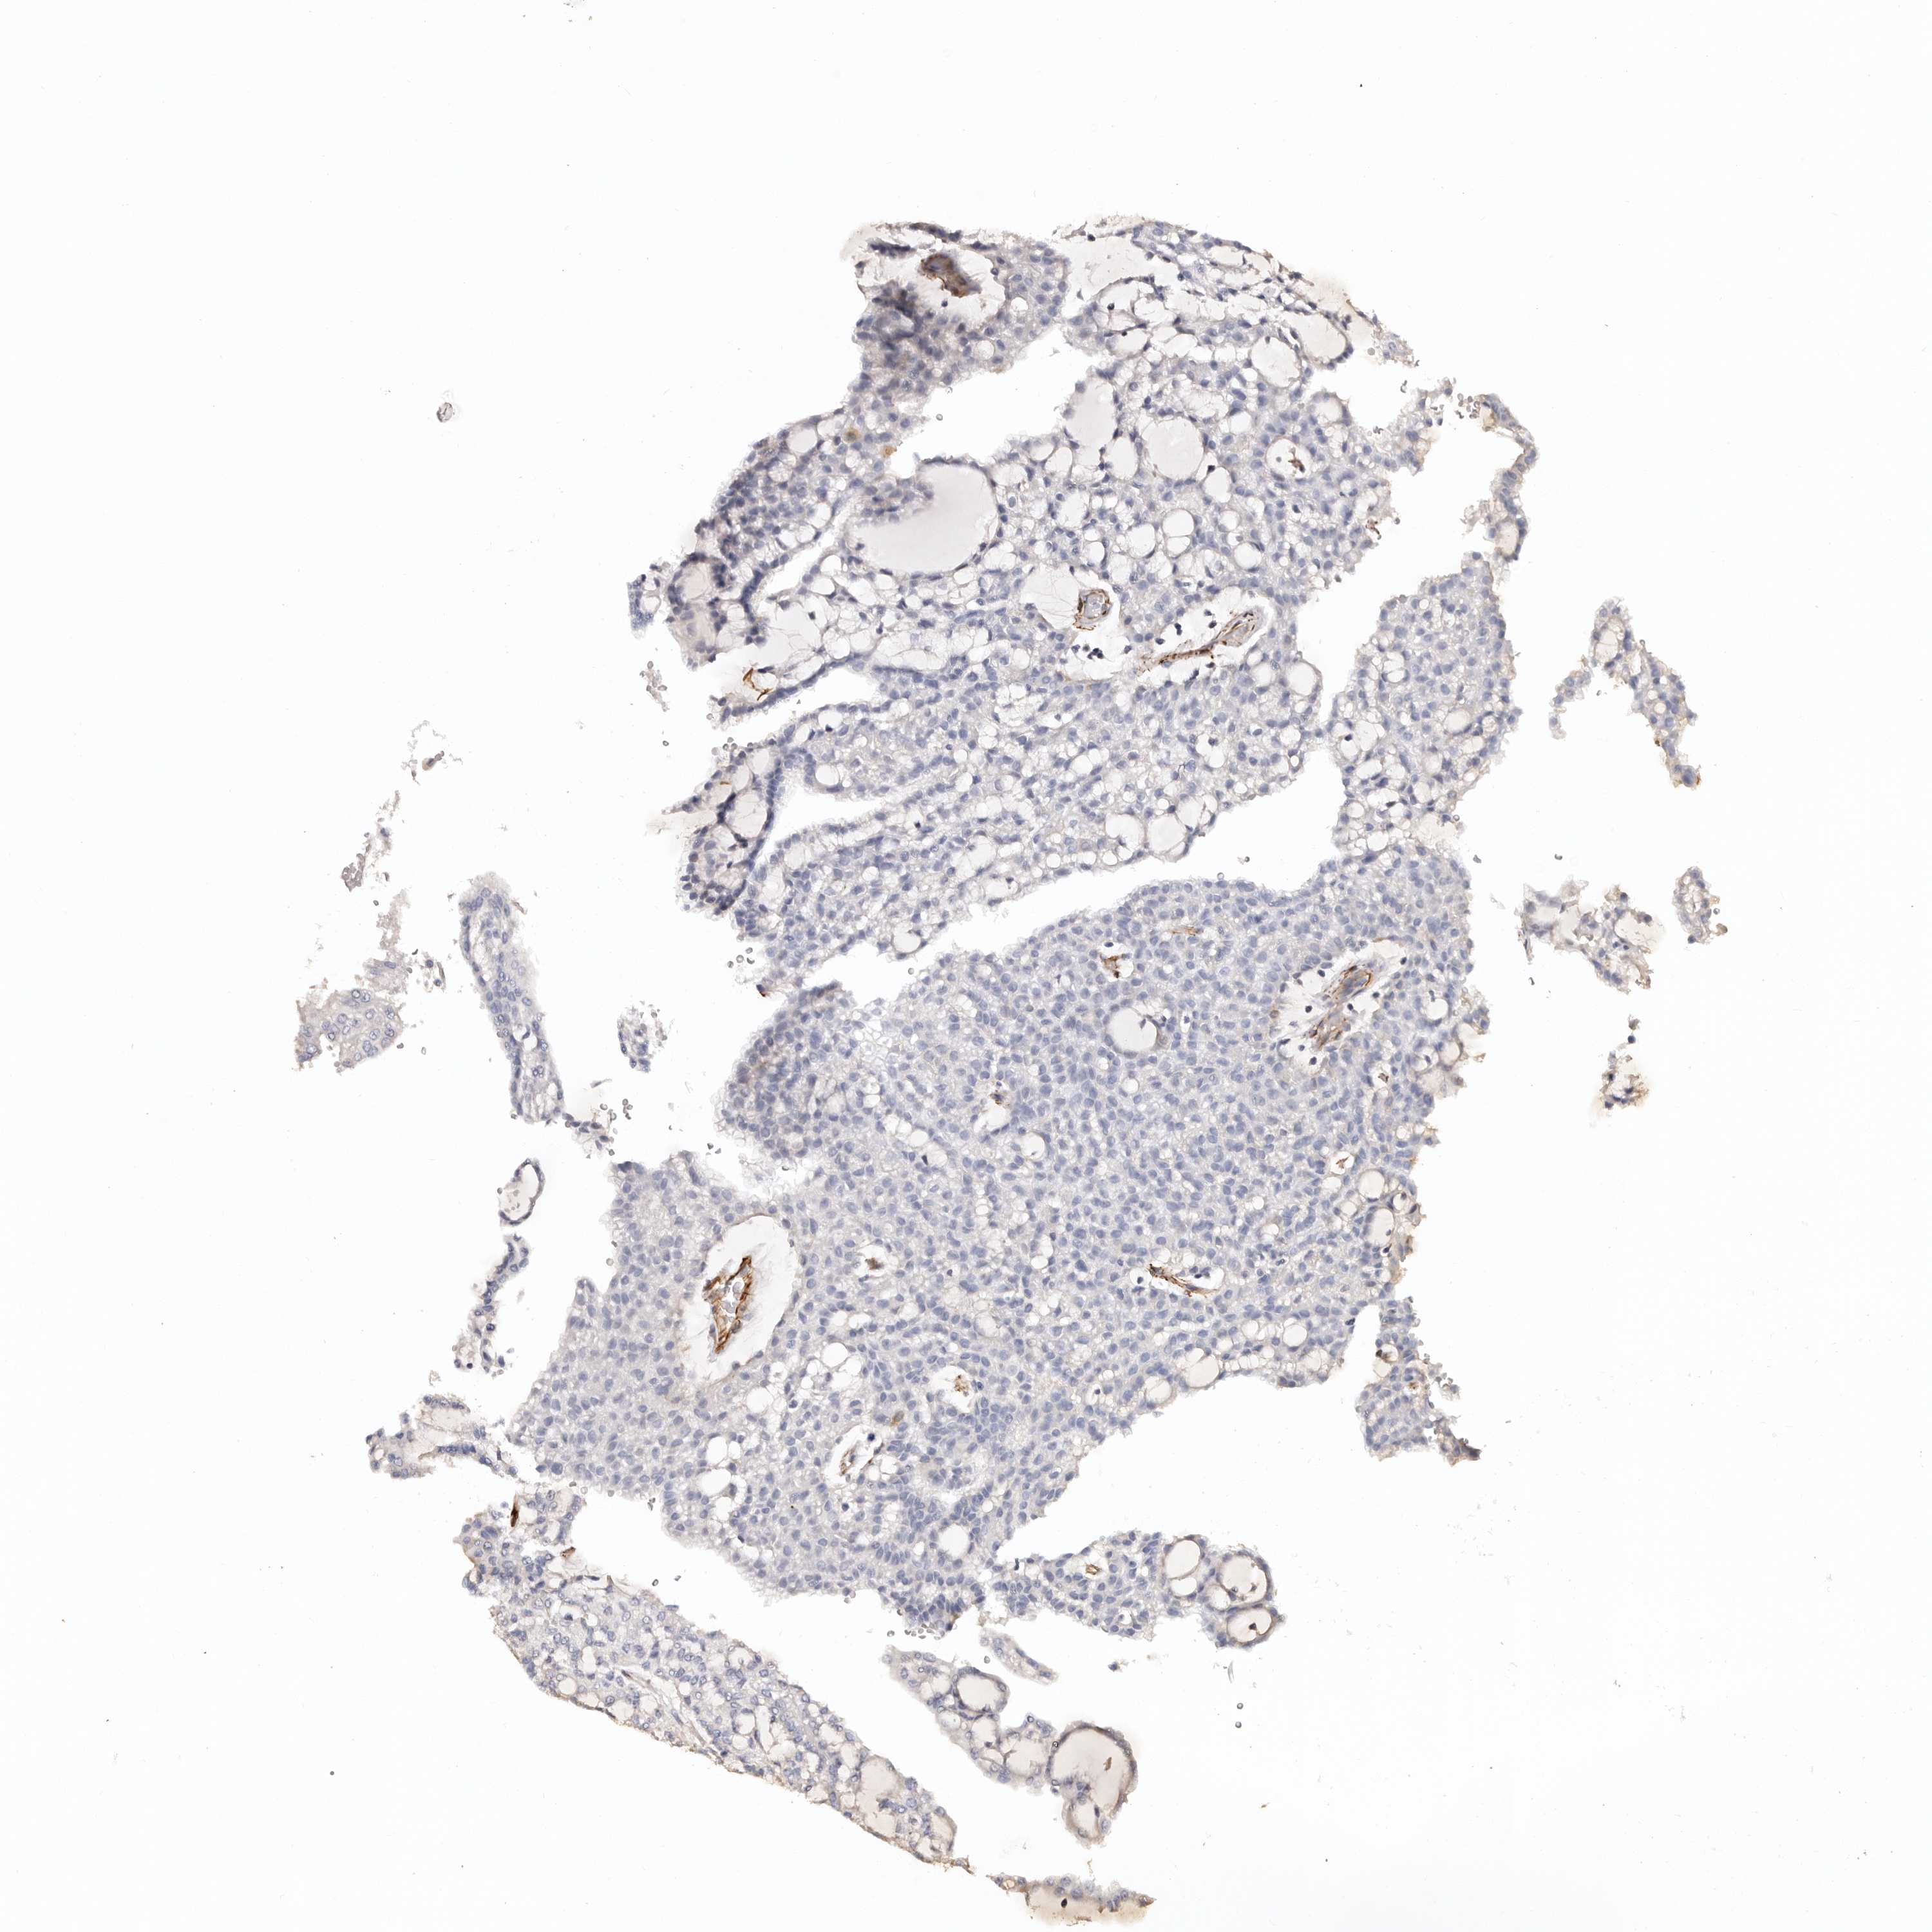

KIDNEY RENAL CLEAR CELL CARCINOMA (VALIDATION) - Interactive survival scatter ploti

The Survival Scatter plot shows the clinical status (i.e. dead or alive) for all individuals in the patient cohort, based on the same data that underlies the corresponding Kaplan-Meier plots. Patients that are alive at last time for follow-up are shown in blue and patients who have died during the study are shown in red.

The x-axis shows the expression levels (FPKM) of the investigated gene in the tumor tissue at the time of diagnosis. The y-axis shows the follow-up time after diagnosis (years). Both axes are complimented with kernel density curves demonstrating the data density over the axes. The top density plot shows the expression levels (FPKM) distribution among dead (red) and alive patients (blue). The right density plot shows the data density of the survived years of dead patients with high and low expression levels respectively, stratified using the cutoff indicated by the vertical dashed line through the Survival Scatter plot. This cutoff is automatically defined based on the FPKM cutoff that minimizes the p-score. The cutoff can be changed by dragging the vertical line or by entering a cutoff value in the square labeled "Current cut-off".

Under the Survival Scatter plot the p-score landscape (black curve; left axis) is shown together with dead median separation (red curve; right axis). Dead median separation is the difference in median mRNA expression between patients who have died with high and low expression, respectively. It is calculated as follows: median FPKM expression of dead patients with high expression - median FPKM expression of dead patients with low expression. This is intended to aid the user in visually exploring custom cutoffs and the associated p-scores and dead median separation.

Individual patient data is displayed and can be filtered by clicking on one or more of the category buttons on the top of the page. Categories describing expression level and patient information include: high, low, alive, dead, female, male and tumor stages. The scale of the x-axis can be toggled between linear and log-scale by clicking on the "x log" button. Mouse-over function shows TCGA ID, patient information and mRNA expression (FPKM) for each patient.

& Survival analysisi

Kaplan-Meier plots summarize results from analysis of correlation between mRNA expression level and patient survival. Patients were divided based on level of expression into one of the two groups "low" (under cut off) or "high" (over cut off). X-axis shows time for survival (years) and y-axis shows the probability of survival, where 1.0 corresponds to 100 percent.

ZNF557 is potential prognostic, high expression is favorable in Kidney Renal Clear Cell Carcinoma (validation)

: 2.28

Average pTPM 2.3

Number of samples 100